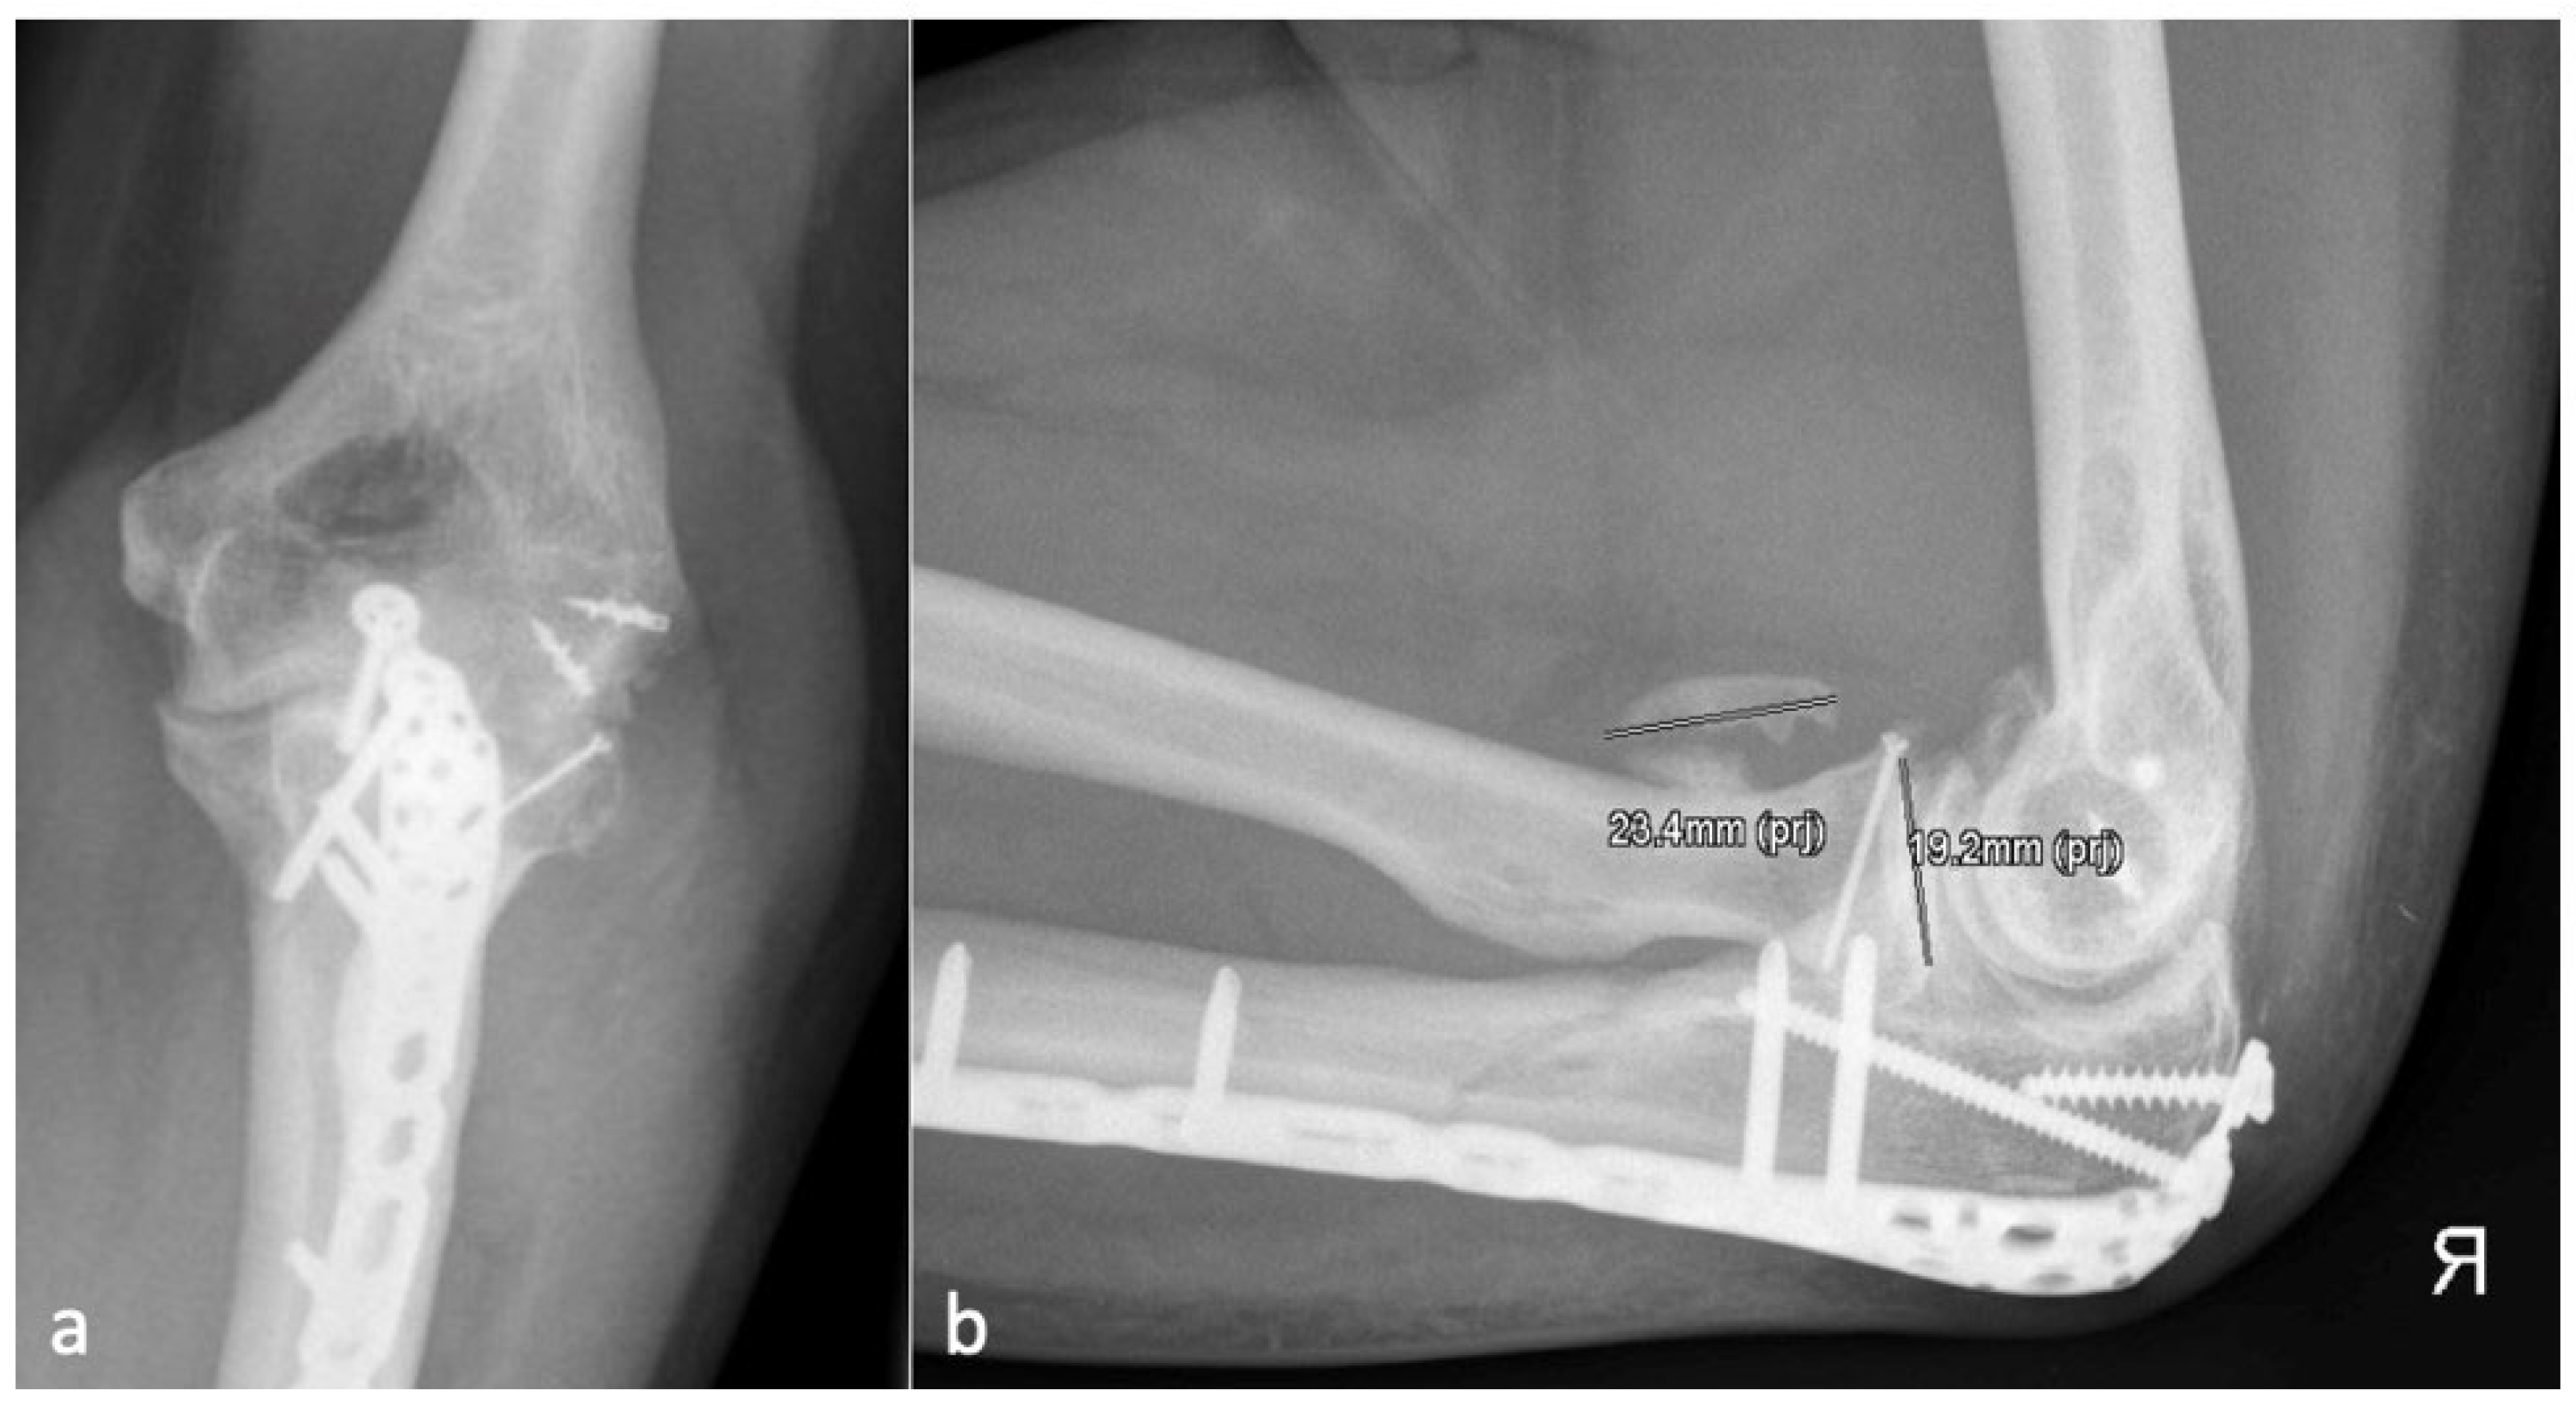

Figure 2.

(a) The AP and (b) the lateral X-ray with a radial HO smaller than the diameter of the radial head, which represents an HO 1 r.